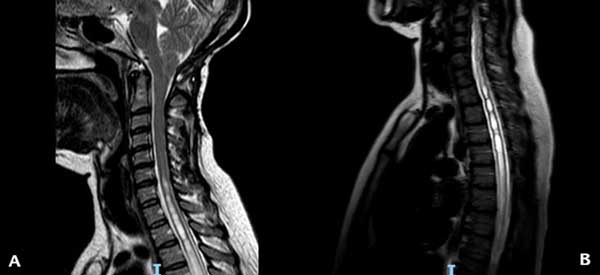

En el momento de la consulta, el examen físico presentó una leve paresia distal en ambos miembros superiores, hipoestesia termoalgésica en la mano y región subescapular izquierdas e hiperreflexia en ambos miembros inferiores. La resonancia magnética (RM) de encéfalo y columna cervical mostró un descenso marcado de las amígdalas cerebelosas con siringomielia cervicodorsal (Figura 1). Luego de la administración de contraste, se observó un refuerzo difuso de las meninges y senos venosos compatibles con hipotensión intracraneana (Figura 2). Ante la sospecha de una fístula espinal espontánea de LCR, se decidió realizar un estudio contrastado intratecal para determinar el sitio de la pérdida.

Figura 1. RM ponderada en T2 que muestra en (A) el descenso amigdalino y la siringomielia cervical y en (B) la extensión de la siringomielia a nivel torácico.